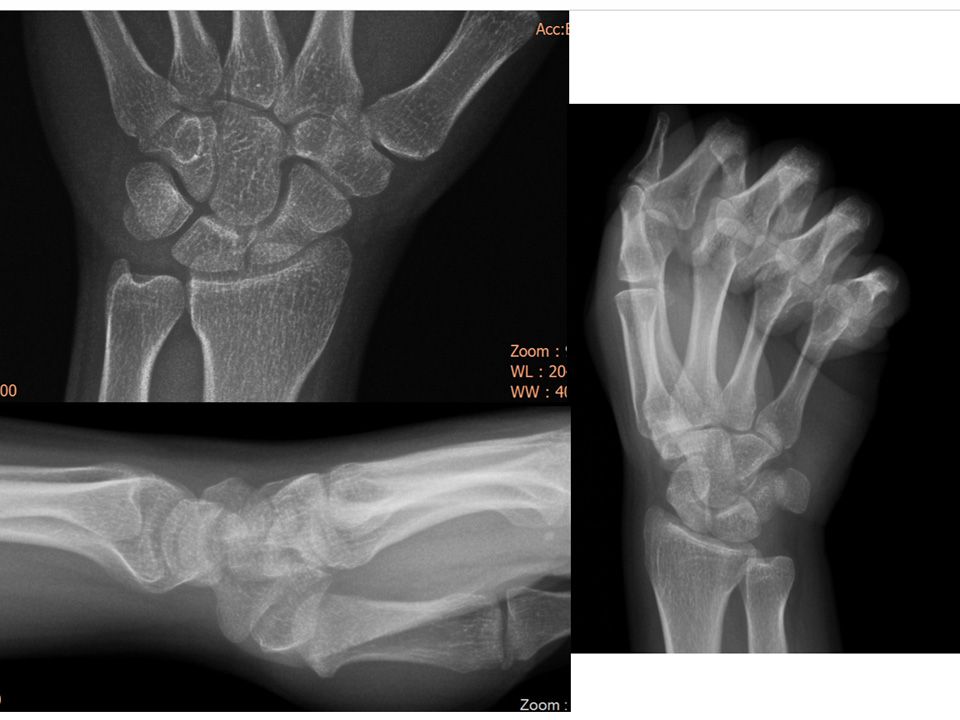

22 yr, female, housewife, right hand dominancy Pain at dorsal aspect of right wrist due to fall on an outstreched hand No pain relief after NSAIDs, rehabilitation and splinting Finger extension test +